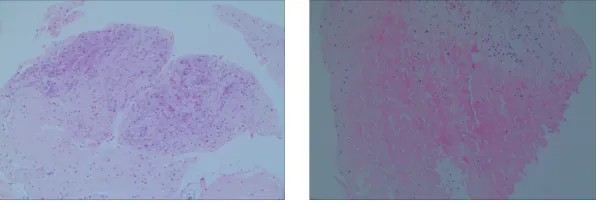

步骤三、专业病理诊断,规范判读评分:

病理科主任高立永非常重视风湿免疫科这一新技术,带领团队给予临床大力支持,24小时后做出了精准的病理诊断:(膝关节滑膜)镜下滑膜组织表面滑膜细胞可见,基质内部分淋巴细胞,浆细胞偶见,血管增生扩张充血,符合炎性关节炎。

据任义乐介绍,国际最新病理研究进展提示,类风湿关节炎滑膜病理一般分为3类:寡免疫型、弥漫髓系型、淋巴髓系型。寡免疫型病理特征是滑膜炎症细胞浸润较少,免疫细胞浸润不显著;弥漫髓系型病理特征是滑膜炎症细胞广泛浸润,但缺乏明显的淋巴滤泡样结构;淋巴髓系型病理特征是滑膜组织中出现类似淋巴结的生发中心结构,这些结构由B细胞和T细胞组成。

任义乐和高立永根据患者临床表现和滑膜炎症细胞浸润较少的滑膜病理特点,共同判断江某滑膜病理类型为寡免疫型。